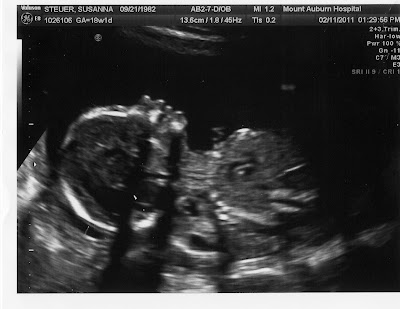

I had my 18 week appointment in early February and everything looks GREAT/PERFECT with Baby #3! They asked me if I wanted to know the gender (both the technician and the doctor) and I gritted my teeth and said a very firm, "NO!" So the first time in my life, practically, I left somewhere, not knowing something that I could have known..very hard for me... So we do NOT know the gender of our baby #3, nor will we until July 7th...my scheduled c-section date. So all are free to guess if you wish! Most have predicted a boy...which is my prediction and always has been...we shall see though!